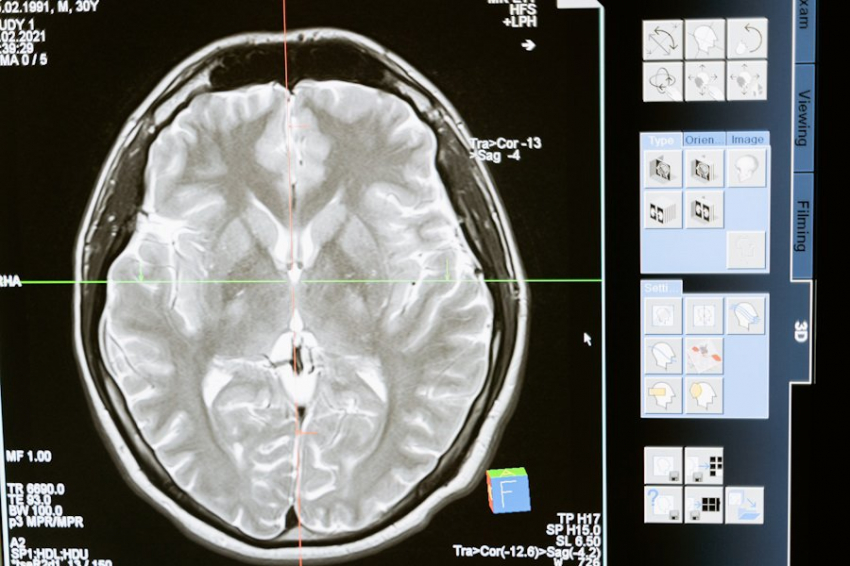

Фото из открытых источников Сладкое повышает уровень глюкозы в крови, которая является важным топливом для мозга. Но ученые пришли к выводу, что если в организме нарушена способность правильно усваивать сахар, что часто происходит при чрезмерном употреблении сладкого, это может привести к сахарному диабету. Недавно исследователи установили, что у людей с диабетом вероятность развития деменции, в том числе болезни Альцгеймера, значительно выше. На основе этих данных была выдвинута гипотеза, что